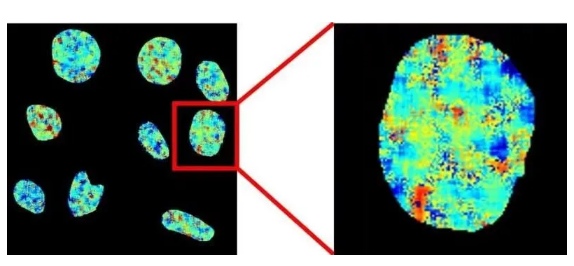

能够检测DNA四联体的探针

图片来源:Smith et al., Science

DNA分子一般呈双螺旋结构,但在人体癌症细胞中,DNA有时会形成包含四股DNA链的G-四联体(G-quadruplex)结构。一项《自然·通讯》上的研究开发了名为“DAOTA-M2”的荧光探针,在活细胞中检测DNA的G-四联体。与G-四联体结合后,探针发出的荧光持续时间就会变长。他们利用该探针探究了G-四联体和两种螺旋酶(helicase)的相互作用,并发现若从细胞中剔除螺旋酶,会使得G-四联体的水平上升。这一新探针为直接观察活细胞中的G-四联体提供了简便的方法。